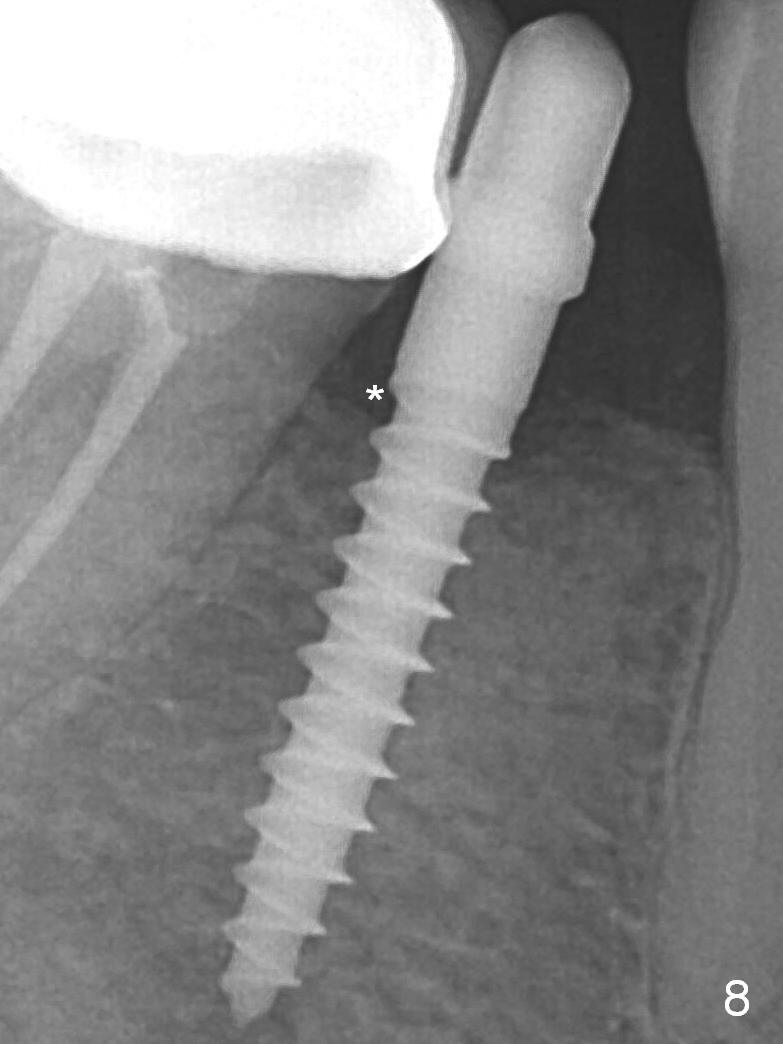

A 2.5x12(2) mm 1-piece implant is placed (Fig.6). There is mild bone loss distal 4 months postop (Fig.8 * (possible artifact due to angulation)). No continuous bone loss 15 months post cementation (Fig.9). There is mild bone resorption mesially 2 years 3 months post cementation (Fig.10).